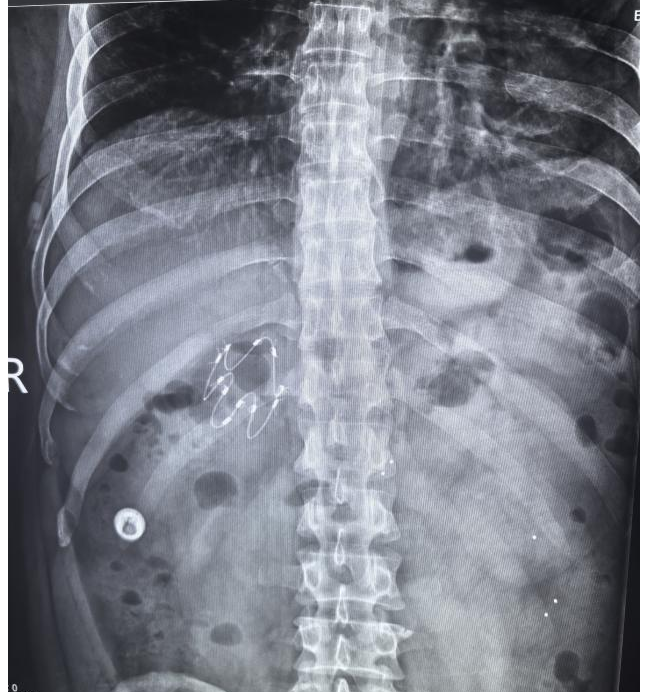

患者李先生,40岁,长期受肥胖困扰,BMI34.5kg/m2属中度肥胖,尝试多种减重方案均效果欠佳,经南院区消化内科团队评估后,认为其适合内镜下胃减重支架置入术。该微创介入技术无需开刀、创伤小、恢复快,且支架可日后取出。消化内科医疗团队与李先生及家人充分沟通后,决定于11月14日行胃减重支架置入术。手术仅用了20分钟左右,过程也并不复杂,术后李先生仅感咽部轻度不适。为避免早期并发症,医生耐心讲解并叮嘱李先生术后饮食需从流食逐渐过渡至普通饮食,目前患者一般情况良好,饮食、体重、副反应等关键指标实时监测中,预计3月后行胃镜下支架取出。

术后第1天复查支架位置良好

胃减重支架置入术也称内镜下十二指肠-空肠旁路套管置入术,其原理在于借鉴外科胃转流手术,通过胃镜在十二指肠及空肠上段置入一个60cm的管状套膜,隔离食物与消化酶的接触,改变了食物消化的时间及方式,从而减少食物吸收,一般在支架人体内留置3个月,之后通过胃镜取出,相关副反应可耐受。